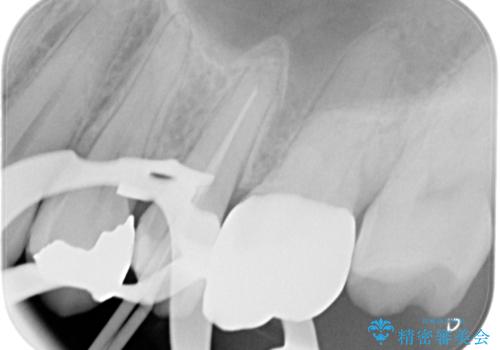

術前に神経の部分壊死と診断しましたが、神経をあけたときに出血が一切無かったので神経が死んでいるという診断は正しかったという事になります。

神経の処置にはマイクロスコープを使用しながら唾液を根管内に入れないようにラバーダムシートを使用しながら治療を行っています。